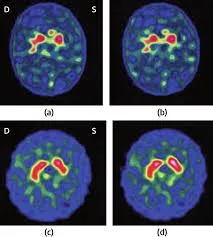

Un recente studio condotto da un team di ricercatori cinesi si è proposto di verificare se le anomalie a scapito del sistema dopaminergico, riscontrate in persone con tossicodipendenza, fossero presenti anche in persone affette da IAD (Hou H. et al., 2012). Al fine di individuare eventuali anomalie nei livelli del trasportatore striatale della dopamina (DAT), è stata utilizzata la tomografia computerizzata a emissione di fotoni singoli (SPECT) (con il radio tracciante 99mTc-TRODAT-1). Il campione esaminato era composto di 5 persone affette da dipendenza da Internet (età media 20 anni), e 9 soggetti di controllo. I pazienti affetti da IAD utilizzavano Internet ogni giorno, trascorrendovi una media di 10 ore. Nessun partecipante aveva mai utilizzato sostanze illecite o soffriva di disturbi psichiatrici e neurologici. Dall’analisi dei risultati della SPECT è emersa una alterazione dei livelli di espressione del trasportatore striatale della dopamina nei soggetti affetti da IAD rispetto al gruppo di controllo.

Fig. 4 – Confronto tra immagini di SPECT di un soggetto con dipendenza da Internet (a) e un soggetto di controllo (b), entrambi ventenni. L’emisfero cerebrale sinistro è raffigurato nella parte destra dell’immagine. Il soggetto con IAD mostra una significativa riduzione del DAT nello striato; il corpo striato bilaterale è più piccolo e più irregolare rispetto a quello del gruppo di controllo. Fonte: Hou H. et al., 2012.

I risultati di questo studio forniscono evidenze scientifiche che provano come la dipendenza da Internet possa indurre una riduzione significativa dei livelli di DAT nel cervello, e che la IAD sia associata a disfunzioni nel sistema dopaminergico (Hou H. et al., 2012). Inoltre, tali risultati supportano la tesi secondo cui la IAD condivide anomalie neurobiologiche comuni anche ad altri disturbi da dipendenza (Potenza M., 2006).